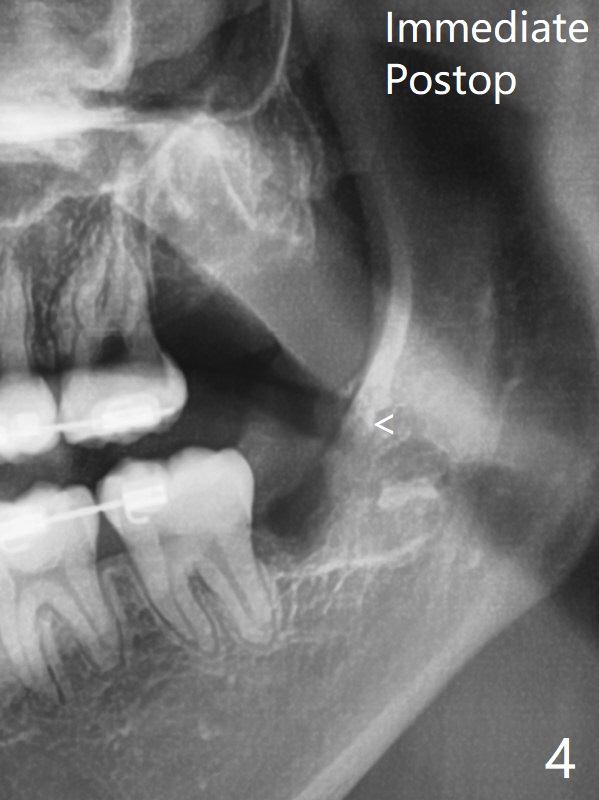

在局麻下拔除4个智齿,由于去骨,显得外斜嵴缺失(图四:箭头),放置胶原塞(防止干槽症),4-0含铬羊肠线缝合,预计外斜嵴6-12月能修复。